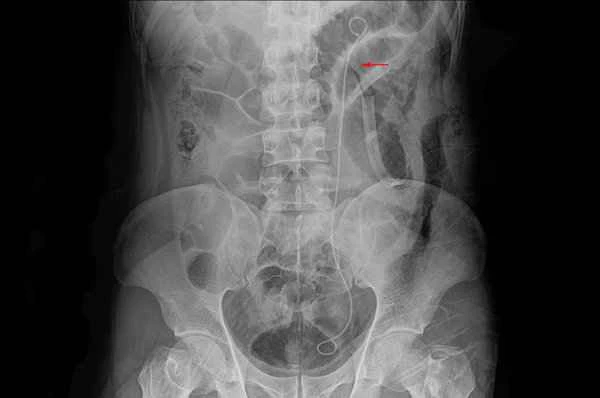

Typical symptoms of intestinal obstruction include severe abdominal pain, abdominal distension, vomiting, and cessation of gas and stool passage. Abdominal pain is usually intermittent and colicky, located in the central or lateral abdomen, and its intensity may vary over time. Abdominal distension occurs because gas and fluid in the intestines cannot pass smoothly, causing significant bloating. Vomiting is often one of the early symptoms of intestinal obstruction; the vomitus may consist of stomach contents or contain bile. Cessation of gas and stool passage is a clear sign of intestinal obstruction, meaning that intestinal contents are not being expelled normally.

Intestinal obstruction may also be accompanied by symptoms such as dehydration, electrolyte imbalance, and fever. The appearance of these symptoms may indicate a more serious condition requiring immediate medical attention. It is important to note that the symptoms of intestinal obstruction can be similar to those of other abdominal diseases. If you experience any of these symptoms, especially if they persist or worsen, you should seek medical attention promptly for professional diagnosis and treatment.